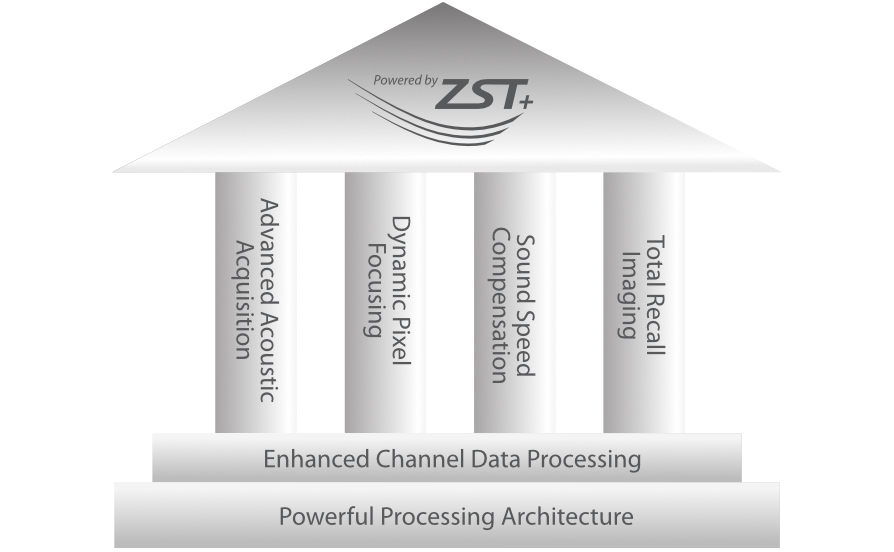

Powered by ZST +

The ZST+ platform represents an extraordinary leap forward in ultrasound technology, moving away from traditional beam-forming to channel data processing. This groundbreaking innovation overcomes the traditional trade-offs among spatial resolution, temporal resolution, and tissue uniformity, resulting in unparalleled image quality that empowers infinite imaging solutions.